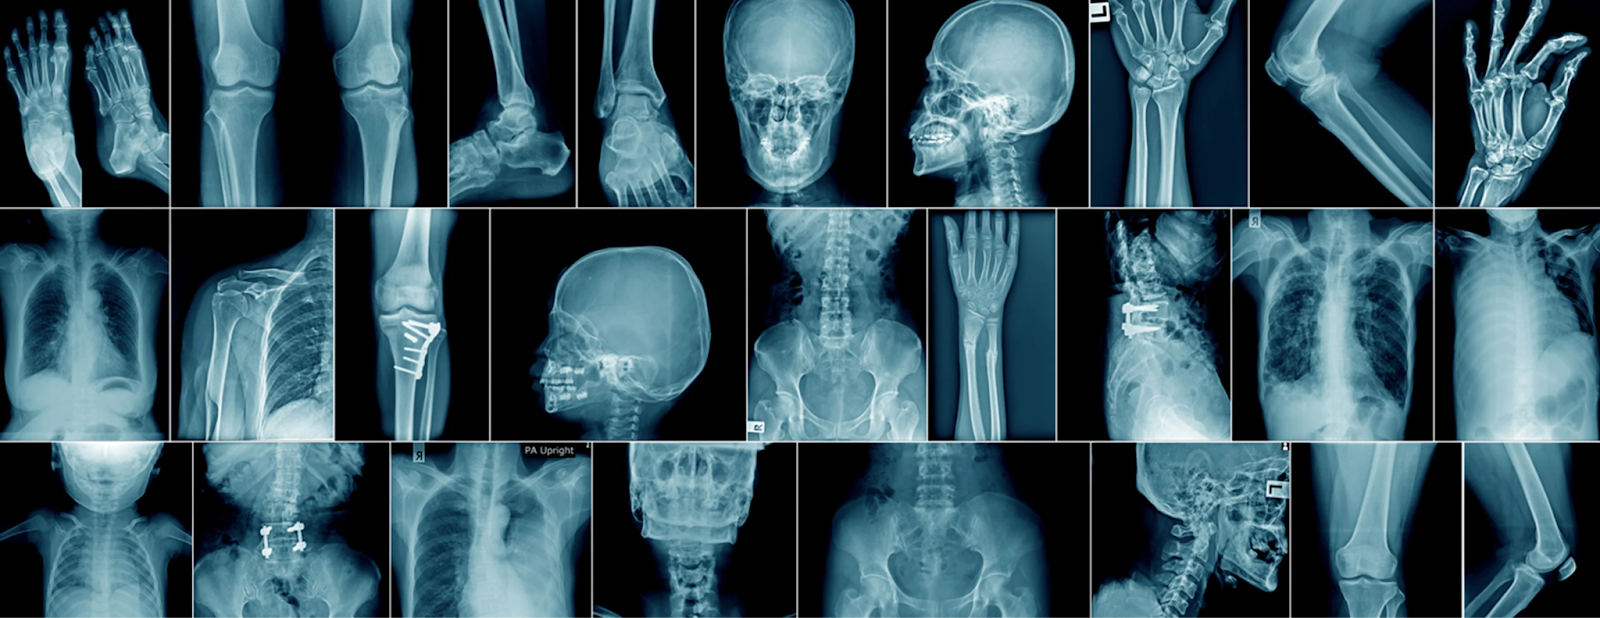

What X-Rays Are Designed to Detect

X-rays work by passing radiation through the body to create images based on tissue density. Dense structures absorb more radiation and appear white on the image.

X-rays are particularly good at identifying:

What X-Rays Cannot Show Clearly

Many sources of pain involve soft tissues, which do not appear well on X-ray images. These tissues have similar densities and therefore do not create enough contrast.